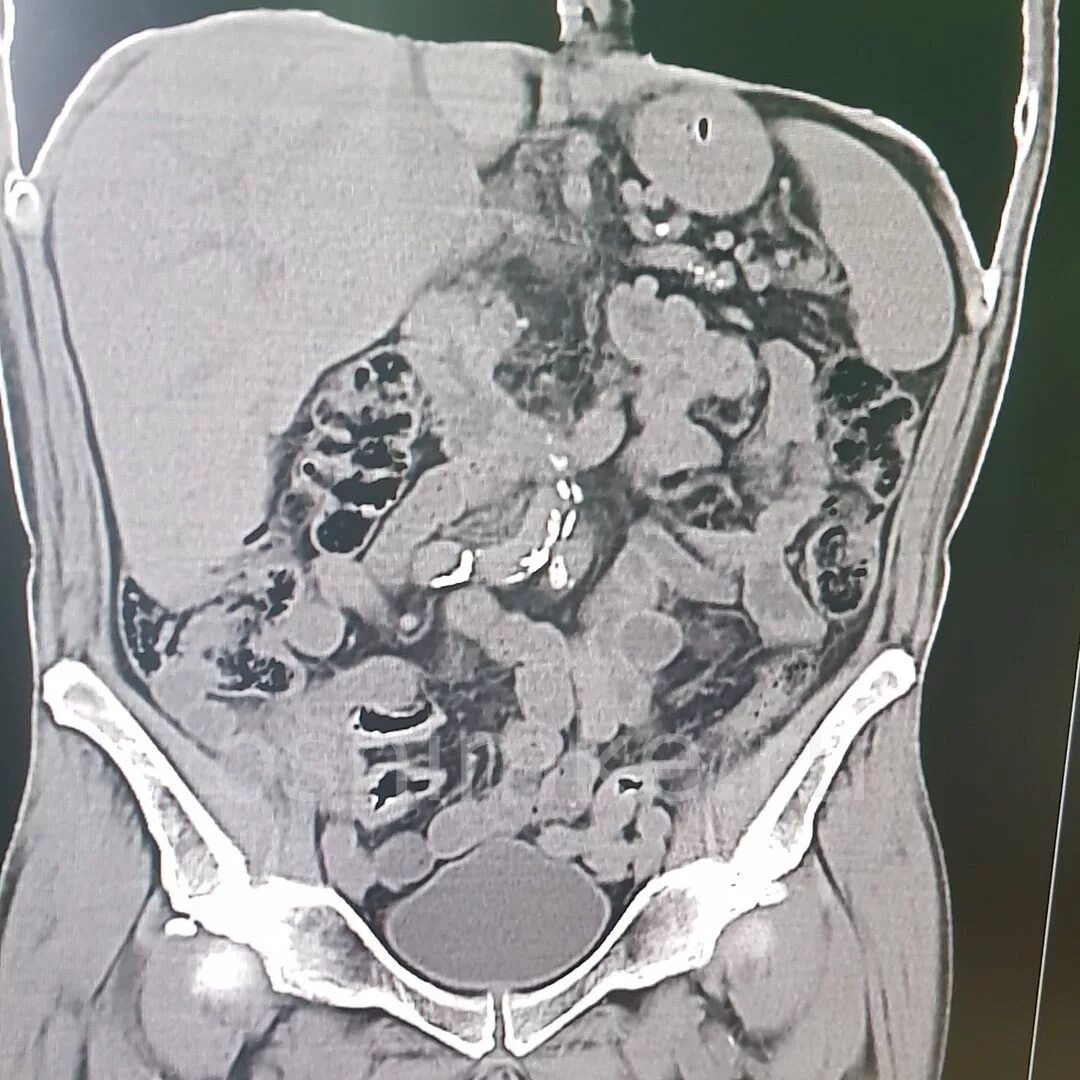

Обследование кт кишечника